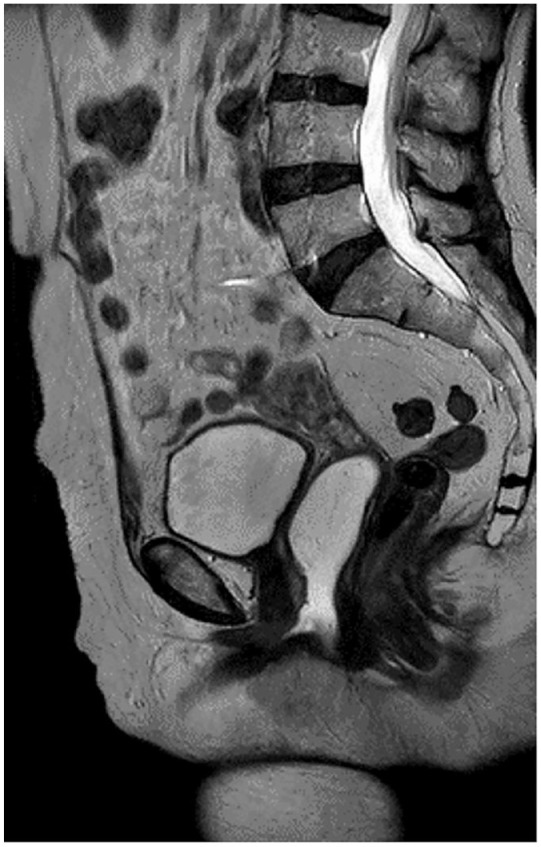

Case presentation: A 52-year-old woman patient arrived with acute urinary retention symptoms that lasted 6 hours. She complained of pain in the perineal and periurethral regions. She struggled with poorly managed type 2 diabetes, metabolic syndrome, and frequent cystitis. The examination showed the presence of a 2-cm stone in the urethra. The treatment utilised retrograde propulsion and laser fragmentation. Postoperative magnetic resonance imaging results were normal, and follow-up care involved managing diabetes and adopting lifestyle changes to prevent the recurrence of cystitis and stones for 6 months.